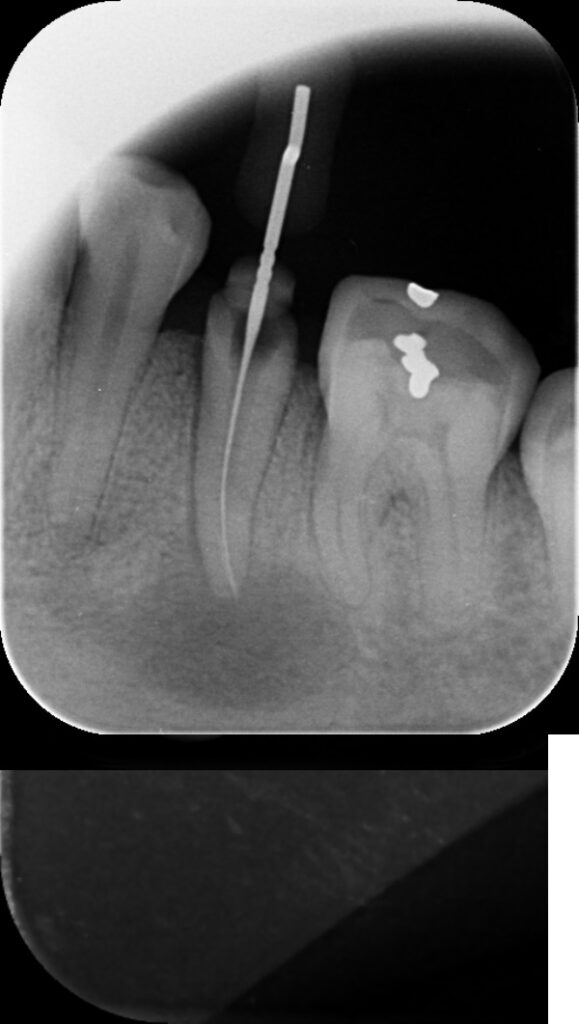

Traitement en cours = Longueur OK